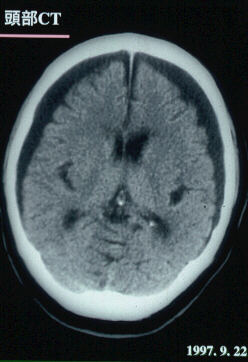

1997.9.22:頭部CTスキャン

ところが、両側に硬膜下血腫が形成された。